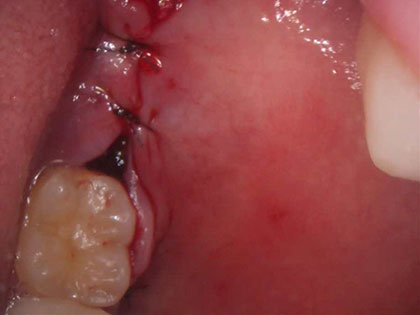

• 抜歯後の写真がこちら

• 親知らずの抜歯治療中1

• 粘膜を開いた部分を糸で縫いました。